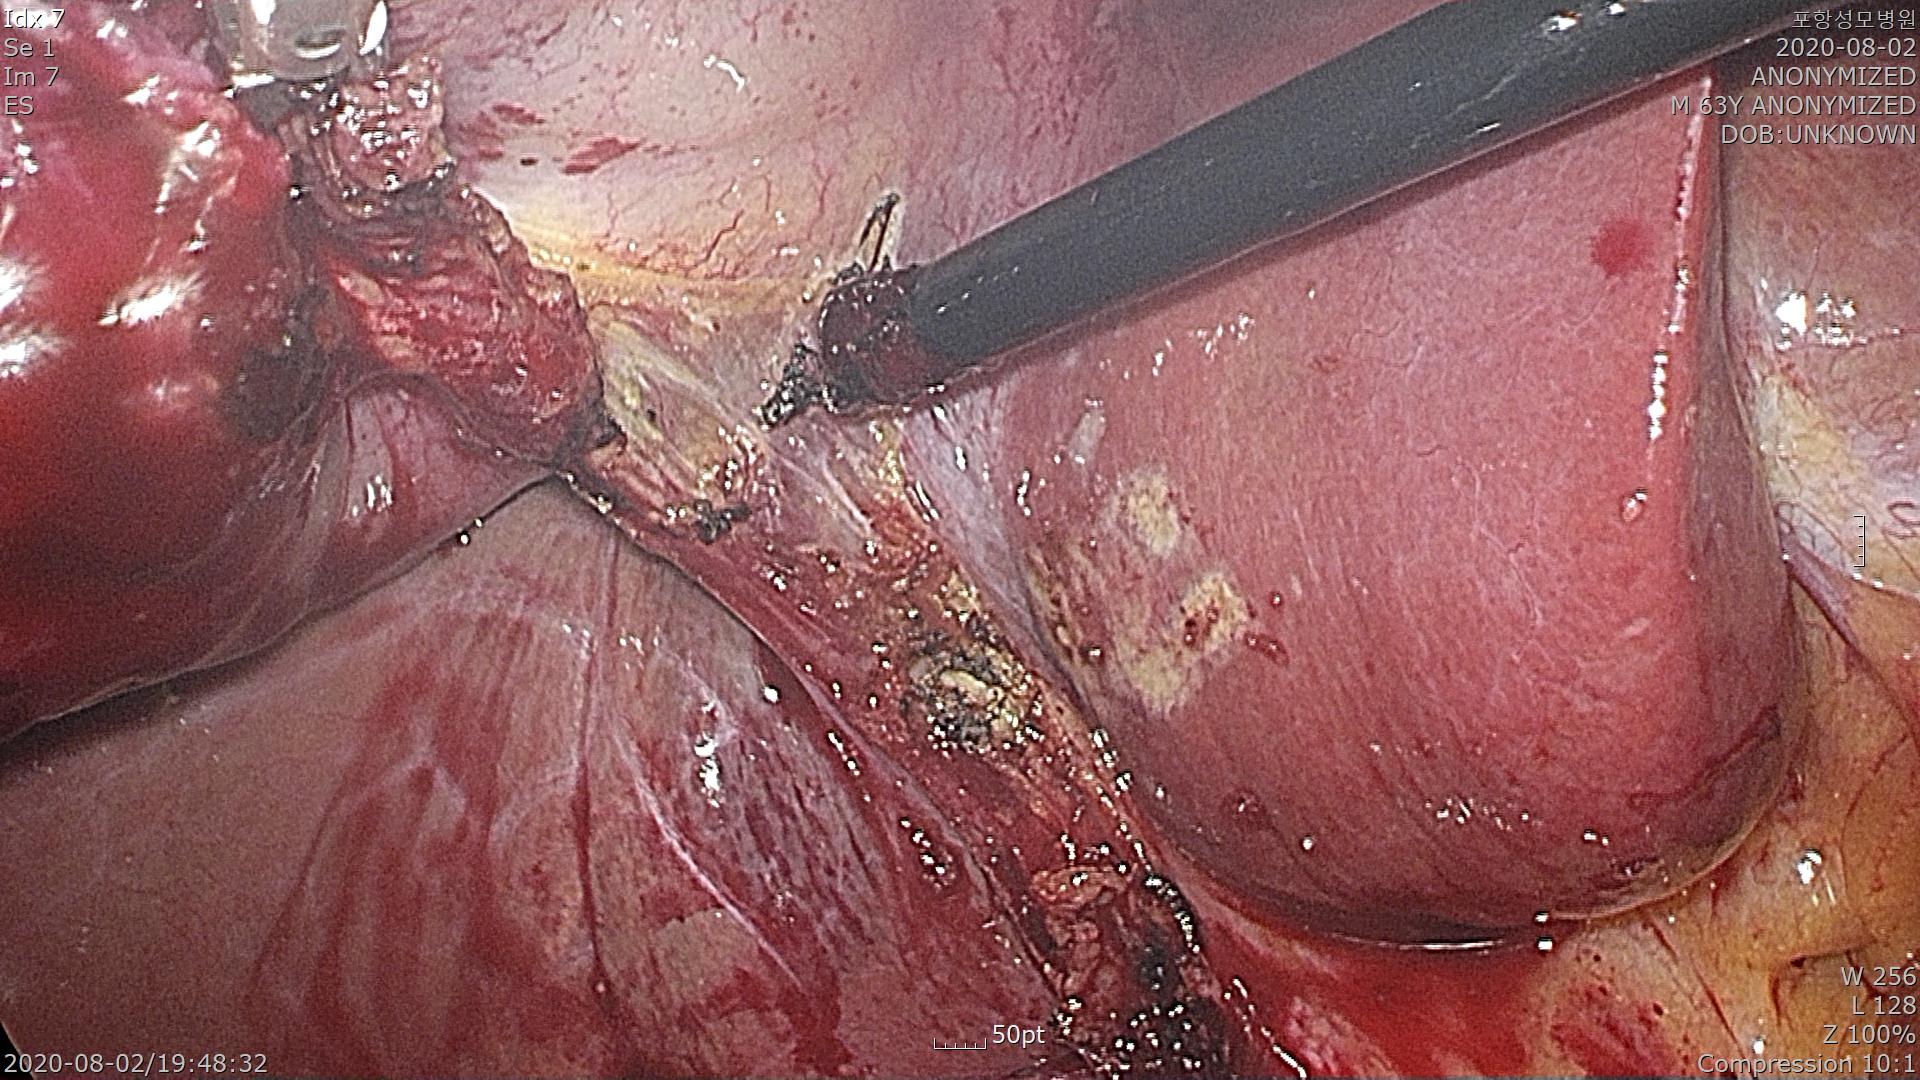

담낭관을 확인하고 박리합니다. 염증이 심해서 출혈이 좀 있습니다.

담낭관을 클립으로 결찰합니다.